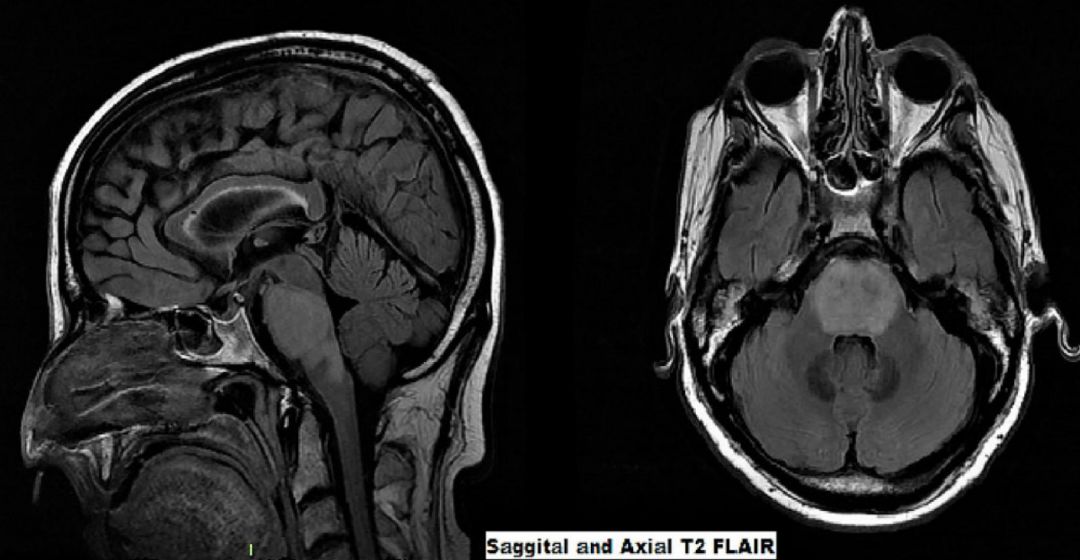

看图识病,文献病例,未提供病史。

答案:弥漫性内生性桥脑胶质瘤(Diffuse intrinsic pontine glioma,DIPG)。

多在儿童期中起病,大多数儿童诊断在5-10岁之间。大多数患者有脑干功能障碍或脑脊液阻塞的迹象,尽管少数肿瘤被认为是偶然发现。通常,症状出现的时间很短(即<1个月),但在诊断前几个月出现全身或细微症状并不罕见。常见的症状包括眼球运动异常或受限、复视、面瘫、笨拙、行走困难、平衡障碍和虚弱。梗阻性脑积水可能会出现颅内压升高的症状和体征。其他症状,包括行为改变、夜惊和学习困难。在磁共振成像上,肿瘤表现为一个巨大的脑干扩张性肿块,而不是一个压迫脑桥的外部肿块。肿瘤经最小阻力途径扩张,可能存在外生成分,但DIPG位于桥脑内,病变累及桥脑大部分。DIPG在T1加权成像上呈低或等信号,在T2加权成像上呈高信号,在Flair序列上常表现为相对均匀。典型DIPG的其他MRI表现包括桥脑腹侧受累和基底动脉包绕。增强无特异性,但病变在诊断时往往没有明显增强。预后极差。